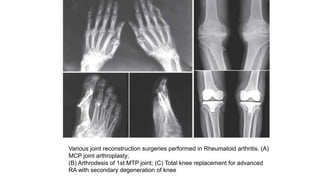

Various joint reconstruction surgeries performed in Rheumatoid arthritis. (A)

MCP joint arthroplasty;

(B) Arthrodesis of 1st MTP joint; (C) Total knee replacement for advanced

RA with secondary degeneration of knee

Surgical Approaches • Synovectomyis ordinarily not recommended for patients with rheumatoid arthritis, primarily because relief is only transient. • However, an exception is synovectomy of the wrist, which is recommended if intense synovitis is persistent despite medical treatment over 6 to 12 months. • Total joint arthroplasties , particularly of the knee, hip, wrist, and elbow, are highly successful. • Other operations include release of nerve entrapments (e.g., carpal tunnel syndrome), arthroscopic procedures, and, occasionally, removal of a symptomatic rheumatoid nodule.

Various joint reconstructionsurgeries performed in Rheumatoid arthritis. (A) MCP joint arthroplasty; (B) Arthrodesis of 1st MTP joint; (C) Total knee replacement for advanced RA with secondary degeneration of knee